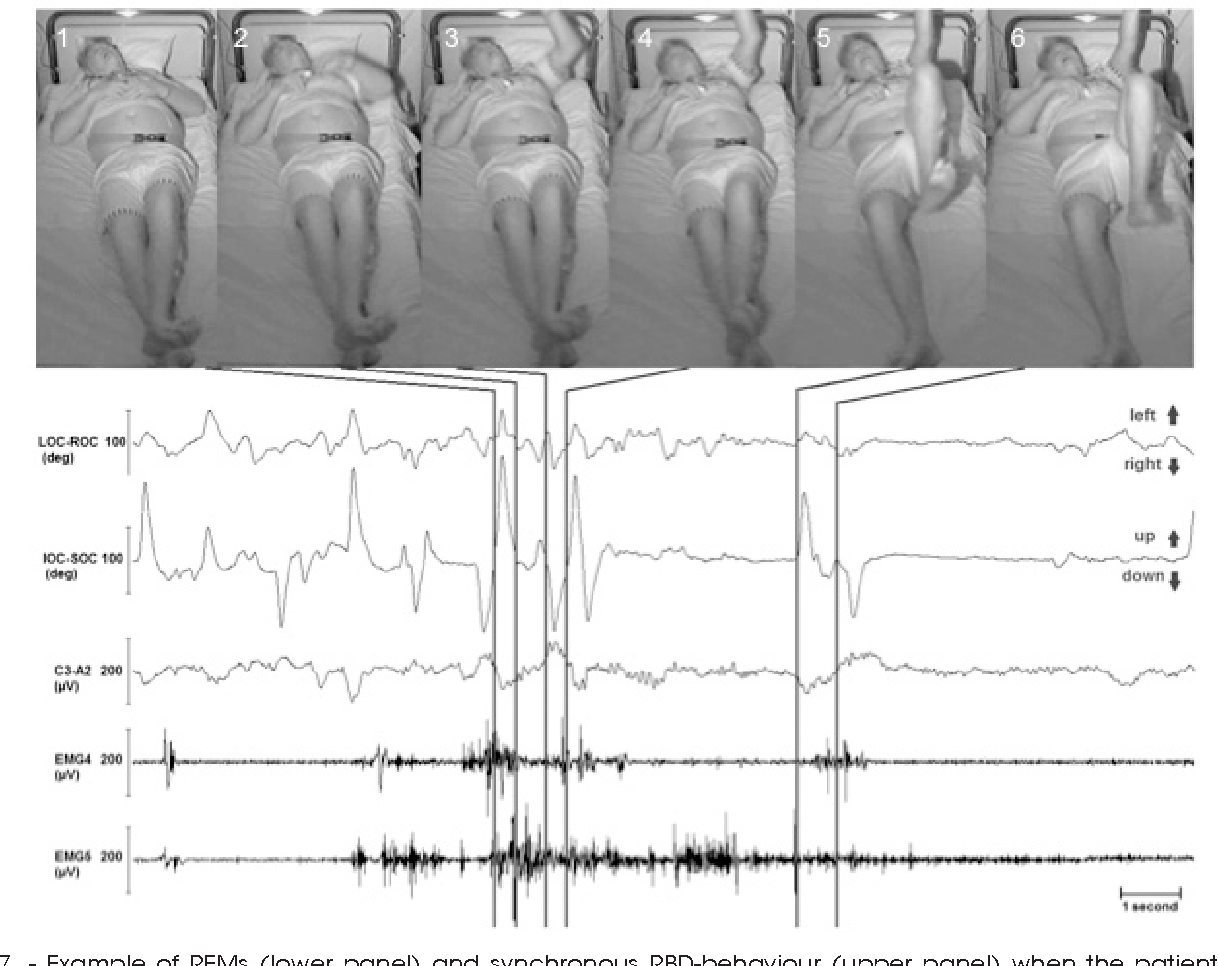

REM (Rapid Eye Movement) sleep is a crucial phase of the sleep cycle, characterized by rapid movements of the eyes, increased brain activity, and vivid dreaming. It accounts for approximately 20-25% of an adult’s sleep time and plays a vital role in cognitive functions such as memory consolidation, emotional regulation, and creativity. Understanding the physiological processes that occur during REM sleep can enhance our appreciation of its importance.

During REM sleep, several physiological changes take place. The brain exhibits heightened activity akin to wakefulness, which can be observed through brain wave patterns. This phase is marked by increased heart rate, irregular breathing, and the temporary paralysis of major muscle groups, preventing the sleeper from acting out dreams. The body experiences a drop in core temperature and changes in hormonal levels, including surges in neurotransmitters like acetylcholine, which promote dreaming. REM sleep typically occurs after about 90 minutes of sleep and recurs multiple times throughout the night, lasting longer with each successive cycle.

In contrast, REM sleep is marked by increased brain activity, rapid eye movements, and vivid dreaming. This stage is essential for cognitive functions such as memory consolidation, problem-solving, and emotional regulation, which differentiates it significantly from the restorative processes occurring during non-REM sleep stages.

Recent advancements in neuroimaging techniques, such as functional MRI (fMRI) and polysomnography, have transformed REM sleep studies. These methods allow for the real-time observation of brain activity during different sleep stages, revealing vital information about the neural mechanisms underlying REM sleep. Additionally, wearable technology has become a valuable asset, providing data on sleep patterns and quality in naturalistic settings.

In sleep medicine, a greater understanding of REM sleep can lead to novel therapies for disorders like REM Sleep Behavior Disorder (RBD) and narcolepsy. For instance, targeted interventions, such as pharmacological treatments that enhance REM sleep, could improve the quality of life for individuals affected by these conditions.